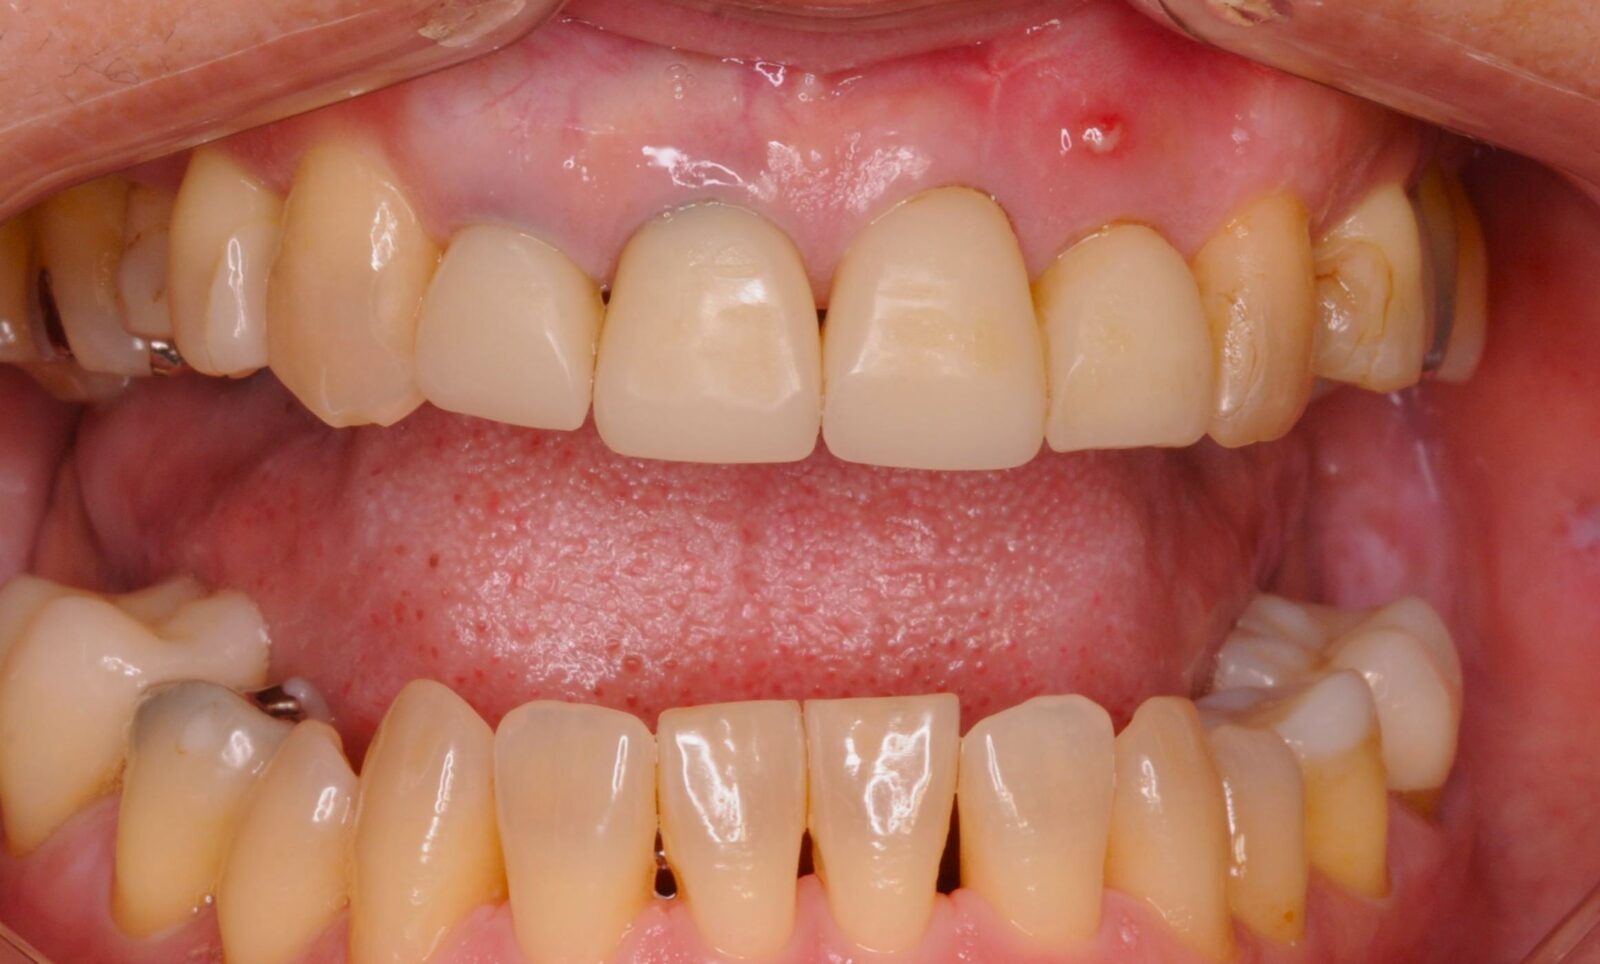

治療前 治療後

上顎前歯部ダイレクトボンディング

以前、他院で充填したコンポジットレジンの変色が気になるとのことで、上顎前歯部6本の充填のやり直し希望。 事前に、模型を作製し、予測完成状態を確認していただき、了承を得たため、治療開始。 ラバーダム下で、旧充填物と虫歯を除去し、自費コンポジットレジンを使用し充填。表面のコーティングと研磨を…